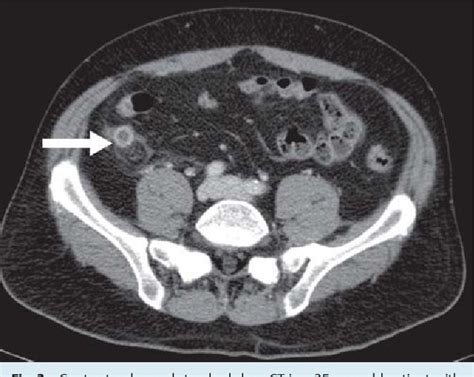

A CT scan can help diagnose appendicitis by visualizing the appendix and surrounding tissues. The scan can show if the appendix is inflamed, ruptured, or blocked, and can also help identify other potential causes of abdominal pain, such as kidney stones or diverticulitis. During the scanning process, patients lie on a table that slides into a large, doughnut-shaped machine, which takes X-ray images of the body from different angles. The images are then reconstructed into detailed cross-sectional images, which are interpreted by a radiologist.